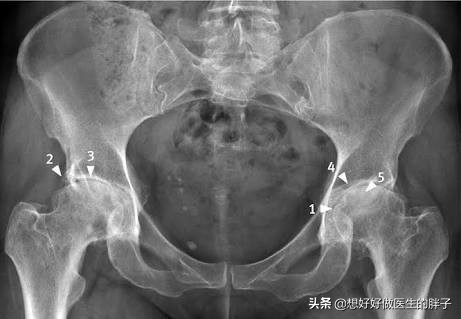

髋关节感到不适的人,需要先查看骨盆的X光片,或者拍摄疼痛部位髋关节的正位和侧位X光片,这样能够初步判断关节间隙是否变窄,是否存在明显的骨质增生,以及髋关节的整体发育状况。假如见到病者关节空隙收窄,常与股骨头腐化或髋关节骨质增生引发的关节空隙软骨破损有关;倘若拍片揭示股骨头与颈相接处有反常的凸起,那么病者大概患有髋关节撞击症。

此外,完成x线检测并不一定意味着完全排除了病情,部分初期病变或髋部软组织异常在影像上难以显现,因此我们建议髋部疼痛者进行髋关节核磁扫描,对于单侧疼痛的情况,更应采用单侧髋关节核磁检查,这种检查能更准确地评估髋臼盂唇是否受损。